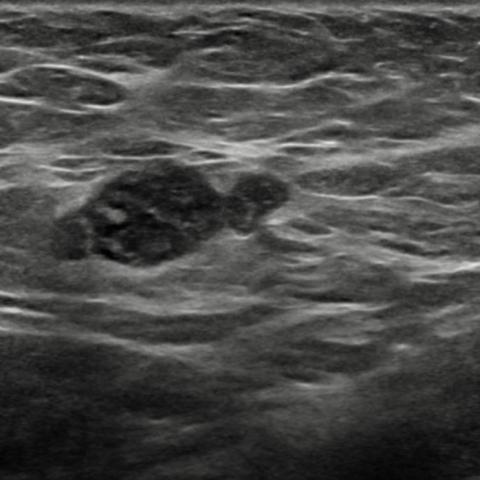

右侧腋窝超声检查可见一个边界清晰的复杂异质性肿块,内部可见小囊性成分以及脂肪回声区域(图8、9、10)。针对这些腋下肿块,建议进一步活检评估。